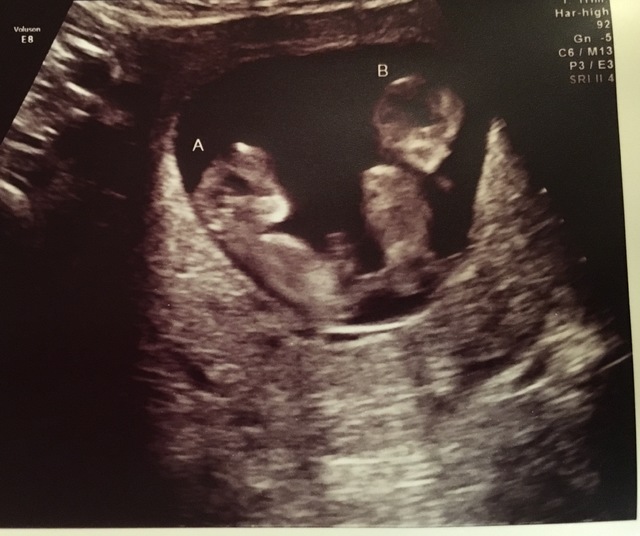

hirdetésKét éve született meg Amanda és férje, Sander Gommans első gyermeke, a tündéri kislány pedig szüleitől a Lana Elise nevet kapta. Az Exit Eden énekesnője később a színpadra is visszatért, a minap azonban újabb örömteli hírt osztott meg követőivel, miszerint ismét áldott állapotban van, ám ezúttal két baba növekszik a szíve alatt.

A nyár elején kiderült, hogy idén másodszorra is anya leszek. Aztán megtudtam, hogy egyszerre két baba van; képzeljétek el Sanderrel, hogy meglepődtünk azon, hogy 2 csecsemőt látunk az ultrahangos képernyőn! Szent ég, ez minden bizonnyal a legnagyobb pozitív sokk, amit valaha átéltem az életemben! Bár tervben volt a családbővítés, nem számítottunk arra, hogy ilyen hamar meg is történik, tehát meglepetés volt a meglepetés tetején. Ajjaj! Ráadásul az is kiderült, hogy egypetéjű ikrek, tehát totál egyformák. Azta! Bár mindez meglehetősen csodálatos, de ez kicsit sem volt könnyű terhesség számomra, sok rosszullétem volt, ezért nagyon nehéz volt lépést tartani azzal, amit meg kellett volna csinálnom. És akkor…